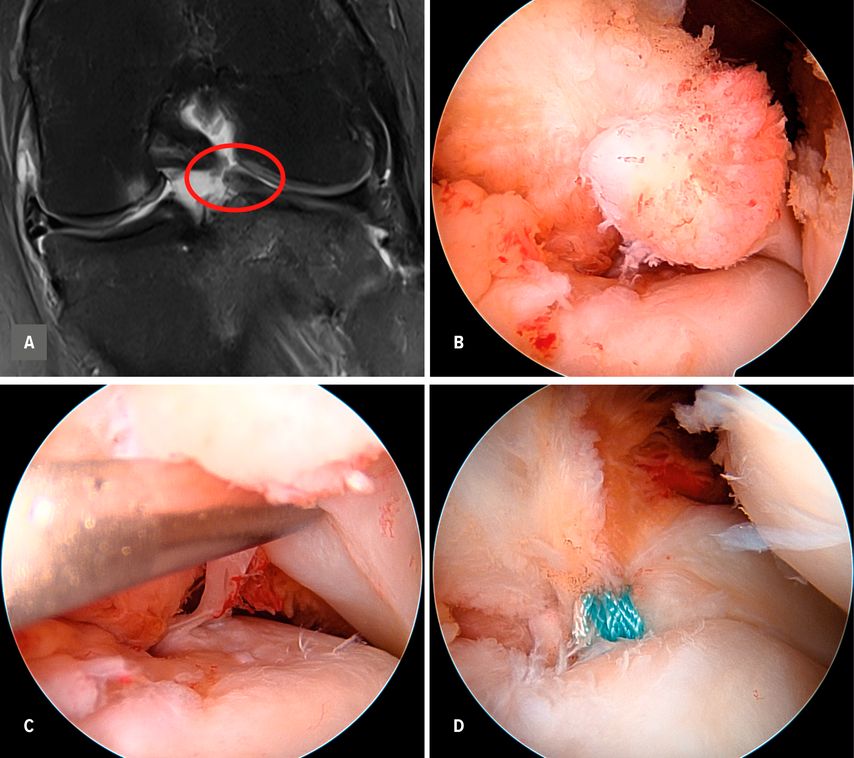

Die heutigen Operationstechniken der medialen Meniskusrefixation umfassen vor allem All-inside-, Inside-out- und transtibiale Verfahren, die durch kontinuierliche technische Weiterentwicklungen und verbesserte Implantate optimiert wurden. Moderne All-inside-Systeme ermöglichen arthroskopische Refixationen mit hoher Primärstabilität und geringer Weichteiltraumatisierung (siehe Beispiel Abb. 1).

Abb. 1: 17-jährige weibliche Patientin mit VKB-Ruptur, komplexem medialem Meniskusriss, Knorpelschaden am medialen Femurkondyl und RootTear der lateralen Meniskushinterwurzel im koronaren MRT (A), arthroskopisch (B,C) sowie nach Refixation (D) mit zwei Fibertapes und tibialem Button